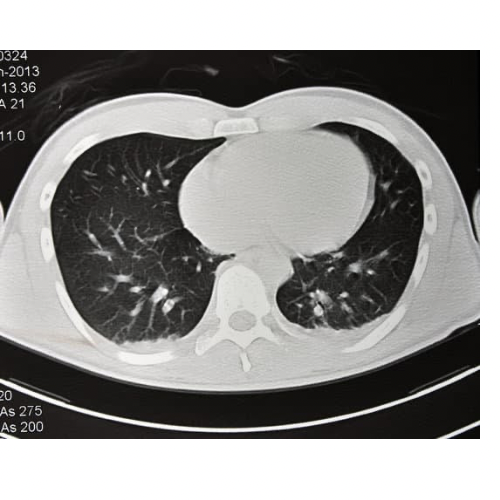

胸部CT

肺の病変を主に観察する検査です。肺炎、肺がん、気胸、肺気腫などの肺の病気の観察をすることができます。